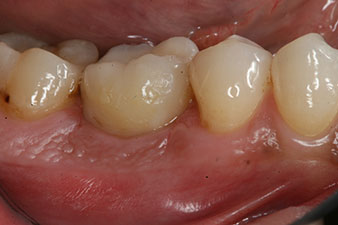

impression

Fig. 8: The impression for the final crown is taken.

Therefore, successful osseointegration and adequate biological stability could be recorded, which enabled an impression to be taken in the same session.

The final pictures show the screw-retained monolithic composite crown in place and the x-ray check (Fig. 9 and 10) (6).